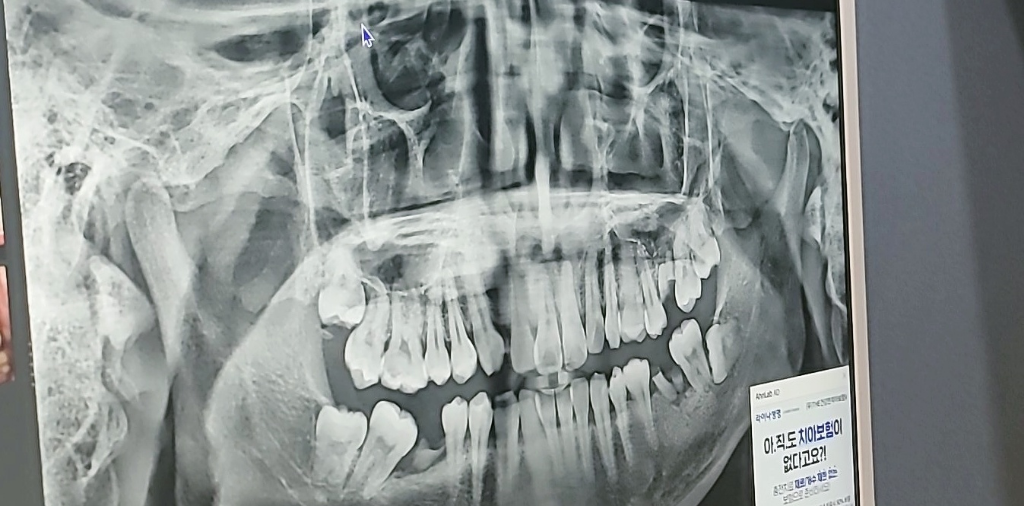

저번주에 오른쪽 어금니쪽 살짝 통증이 있어서 거울을 봤는데 하얀색 비스무리한 것이 보이길래 자세히 보았는데 잇몸을 뚫고 사랑니가 보이더라구요 현재로써는 거의 사랑니가 보여지구요 잇몸이 살짝 덜렁(?) 거린다고 해야하나 현재는 아프지않고 거슬리기만 하는데 꼭 발치해야하나요? 지금은 냅두고 싶습니다 ㅠㅠ 발치해야 될 상황 요건도 갖추어지지 않은 상태여가지구요ㅠㅠ 저번에 치과가서 사진찍었던것 남겨드립니다

• 1번 째 사진

전체적인 치아 상태가 많이 안좋기 때문에 사랑니도 뽑으시고 임플란트 치료도 다수가 필요해보입니다.

사랑니에 대해 먼저 말씀드리자면 양쪽 위,아래로 다 사랑니가 있어서 총 4개의 사랑니입니다. 사랑니의 경우 현재 위치상 그 앞 두번째 어금니 사이로 음식물이 잘 끼게끔 되어 있습니다. 따라서 옆 어금니 충치, 잇몸 부종(치관주위염)등을 유발할 수 있습니다.

사랑니 말고도 전반적으로 뿌리만 남은 치아가 아래 2개 있는데 둘 다 씹는데 중요한 역할을 하는 첫번째 큰 어금니입니다. 그리고 뼈도 많이 녹아있는 상태여서 수직적 높이가 굉장히 낮습니다.

전반적으로 치과를 가셔서 치료계획을 세워보시면 좋을 것 같습니다.

당장 급한건 사랑니 발치보다는 전체적인 치과 치료계획인 것 같습니다. 발치는 치료계획을 세울 때 조금 후순위로 뒤로 미룰 수도 있습니다.